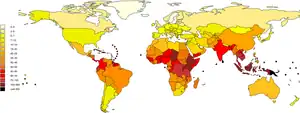

It is estimated that one million severe cases of leptospirosis in humans occur every year, causing about 58,900 deaths.[11] The disease is most common in tropical areas of the world but may occur anywhere.[7] Outbreaks may arise after heavy rainfall.[7] The disease was first described by physician Adolf Weil in 1886 in Germany.[16][17] Infected animals may have no, mild or severe symptoms.[18] These may vary by the type of animal.[15][18] In some animals Leptospira live in the reproductive tract, leading to transmission during mating.[15]

Epidemiology

It is estimated that one million severe cases of leptospirosis occur annually, with 58,900 deaths. Severe cases account for 5–15% of all leptospirosis cases.[11] Leptospirosis is found in both urban and rural areas in tropical, subtropical, and temperate regions.[10] The global health burden for leptospirosis can be measured by disability-adjusted life year (DALY). The score is 42 per 100,000 people per year, which is more than other diseases such as rabies and filariasis.[7]

The disease is observed persistently in parts of Asia, Oceania, the Caribbean, Latin America and Africa.[27] Antarctica is the only place not affected by leptospirosis.[27] In the United States, there were 100 to 150 leptospirosis cases annually.[52] In 1994, leptospirosis ceased to be a notifiable disease in the United States except in 36 states/territories where it is prevalent such as Hawaii, Texas, California, and Puerto Rico.[53] About 50% of the reported cases occurred in Puerto Rico. In January 2013, leptospirosis was reinstated as a nationally notifiable disease in the United States.[52] Research on epidemiology of leptospirosis in high-risk groups and risk factors is limited in India.[54]

The global rates of leptospirosis have been underestimated because most affected countries lack notification or notification is not mandatory.[20] Distinguishing clinical signs of leptospirosis from other diseases and lack of laboratory diagnostic services are other problems.[55] The socioeconomic status of many of the world's population is closely tied to malnutrition; subsequent lack of micronutrients may lead to increased risk of infection and death due to leptospirosis infection.[56] Micronutrients such as iron, calcium, and magnesium represent important areas for future research.[56]